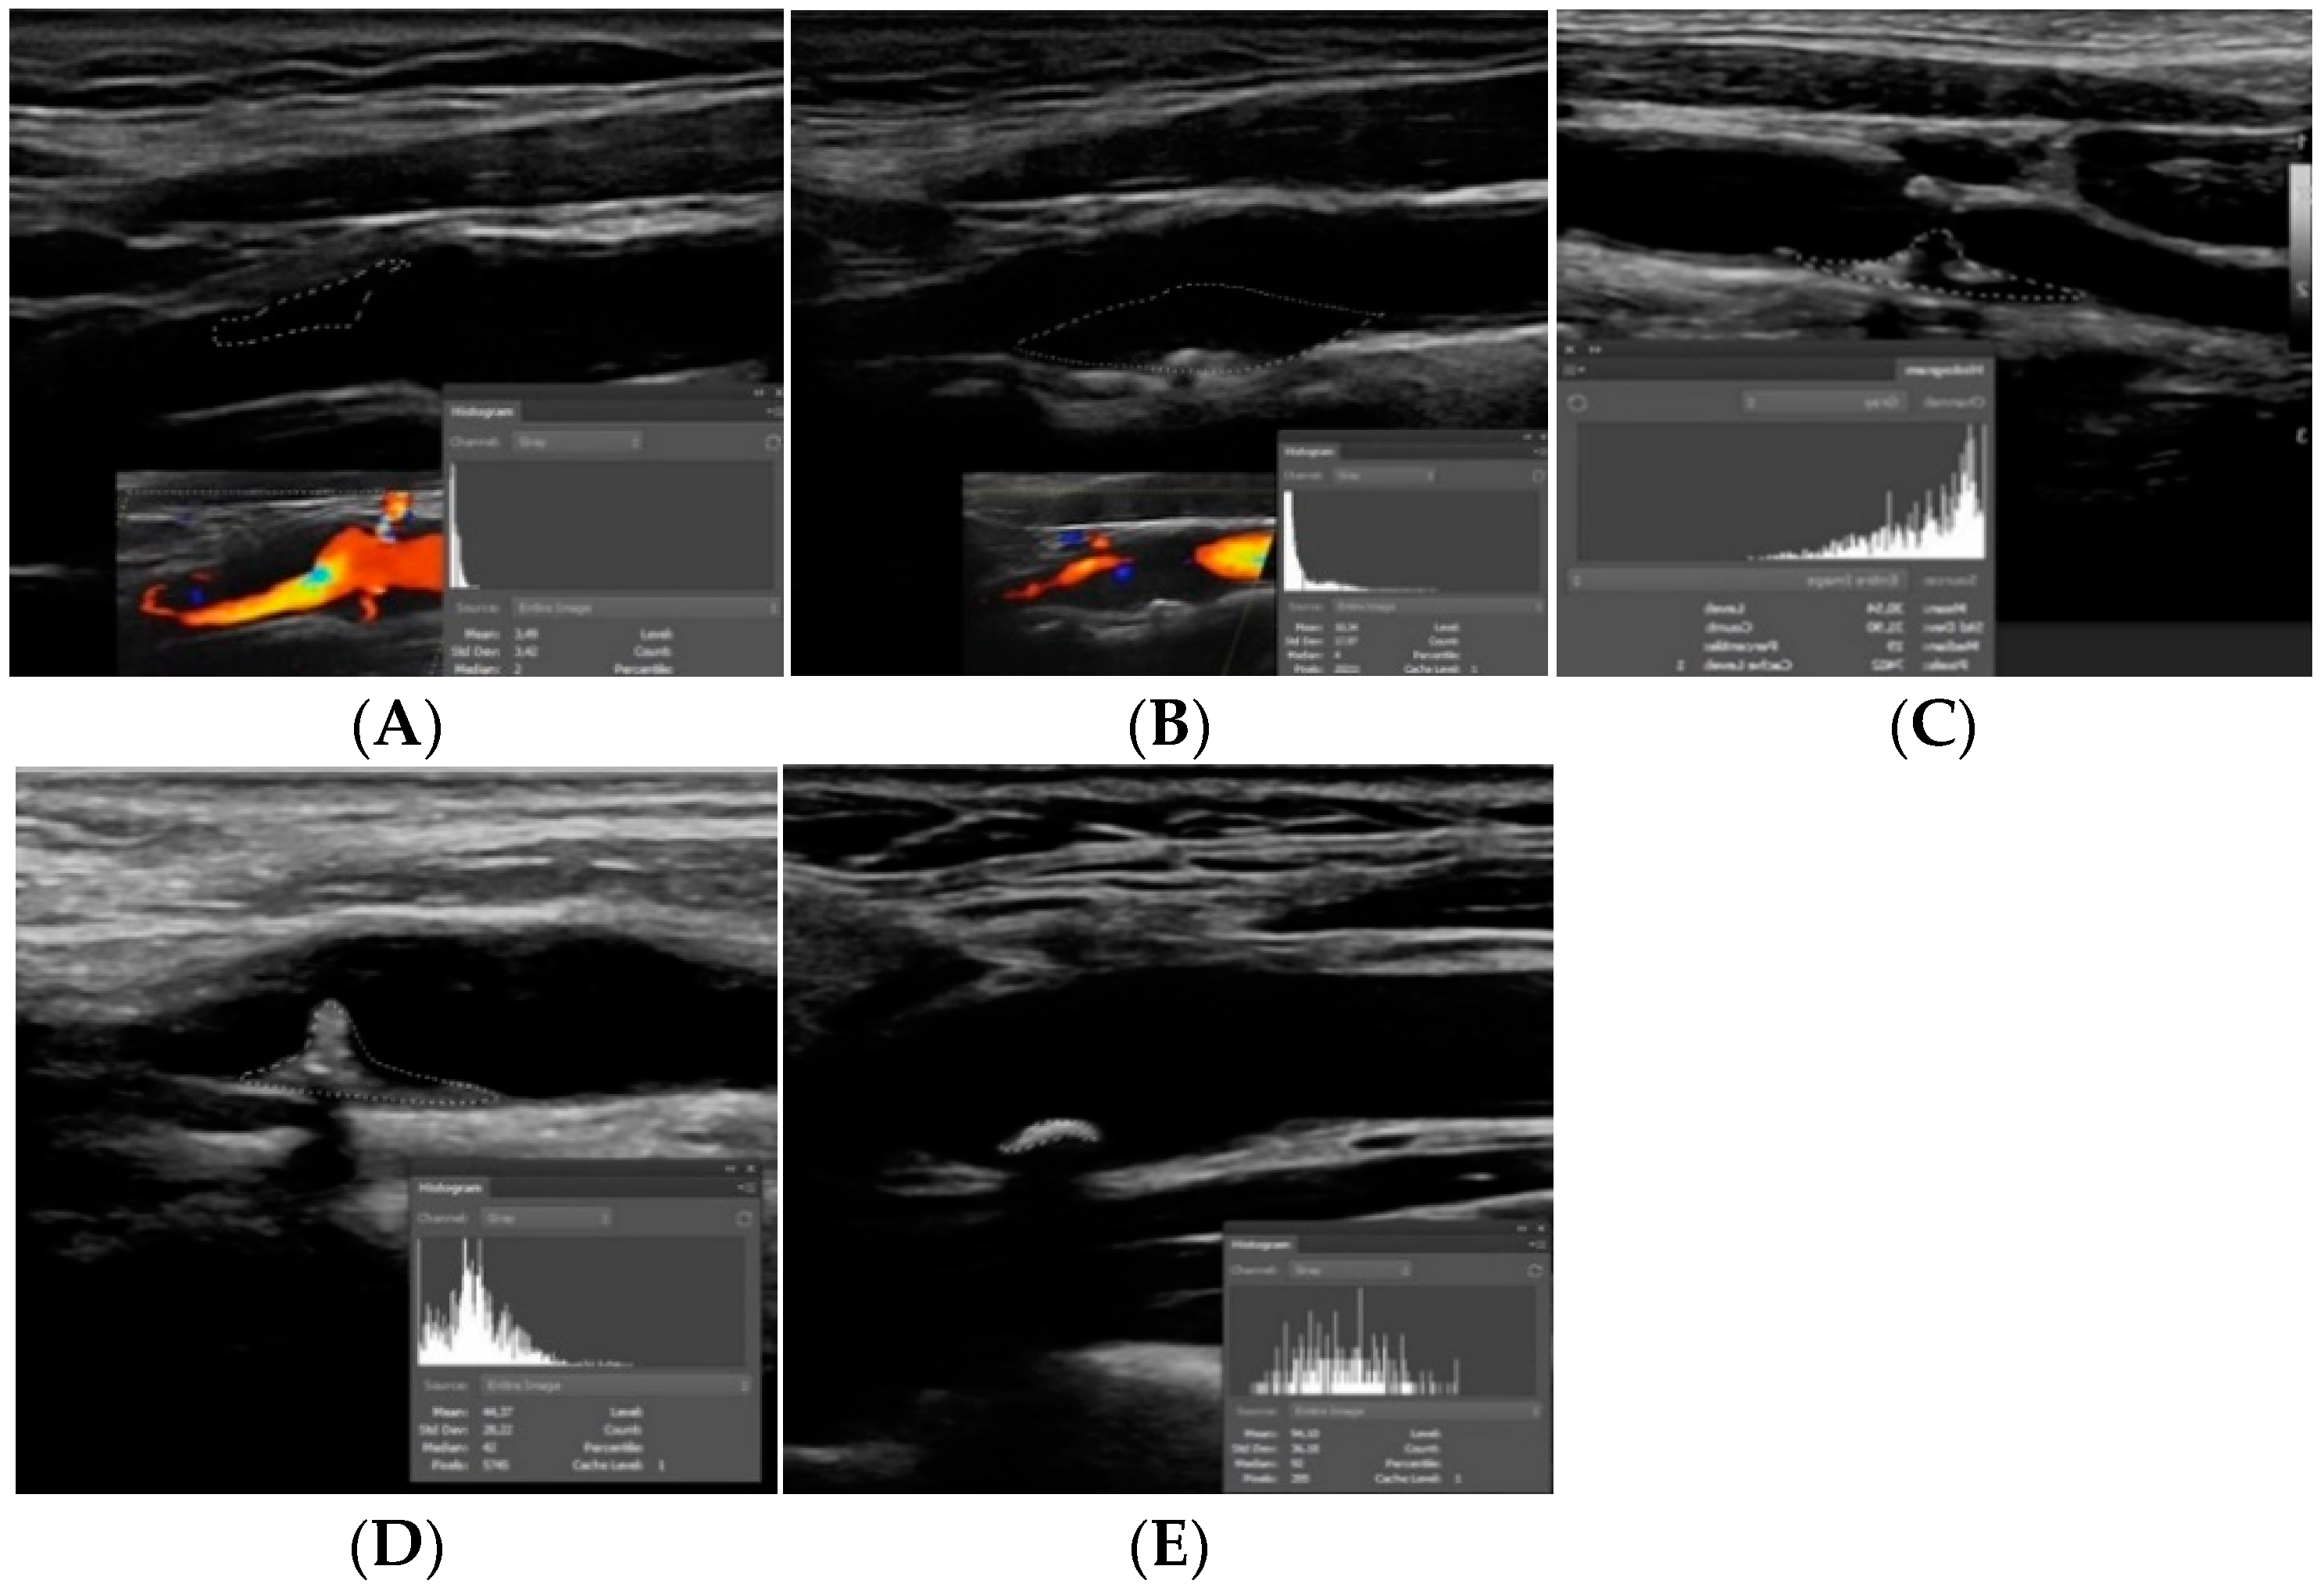

2. Plaque Echogenicity

- Huang, Z.; Cheng, X.Q.; Liu, H.Y.; Bi, X.J.; Liu, Y.N.; Lv, W.Z.; Xiong, L.; Deng, Y.B. Relation of Carotid Plaque Features Detected with Ultrasonography-Based Radiomics to Clinical Symptoms. Transl. Stroke Res. 2021. [Google Scholar] [CrossRef] [PubMed]